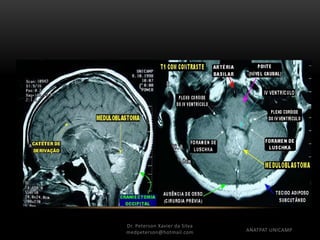

Diagnóstico por Imagem

• RNM

– Heterogêneo em T1, Hiperintenso ou hipointenso em T2,

realce heterogêneo ao contraste, restringe a difusão,

pico de colina a espectroscopia

Diagnóstico por Imagem •Tomografia – Imagem bem definida, linha média em fossa posterior, espontaneamente hiperdenso, realce homogêneo ao contraste • RNM – Heterogêneo em T1, Hiperintenso ou hipointenso em T2, realce heterogêneo ao contraste, restringe a difusão, pico de colina a espectroscopia Dr. Peterson Xavier da Silva Dr. Peterson Xavier da Silva medpeterson@hotmail.com